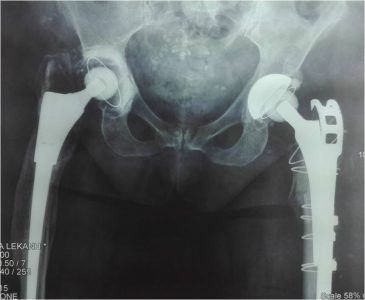

Στην ολική αρθροπλαστική ισχίου αντικαθιστούμε τις κατεστραμμένες αρθρικές επιφάνειες με μεταλλικές προθέσεις τιτανίου, που επιτρέπουν πλήρεις και ανώδυνες κινήσεις της άρθρωσης. Η εφαρμογή των πλέον σύγχρονων μεθόδων μικρής παρεμβατικότητας (MIS) και αποθεραπείας εγγυάται τα καλύτερα δυνατά αποτελέσματα με την άμεση μετεγχειρητική κινητοποίηση, την ολιγοήμερη παραμονή στην κλινική και την ταχύτερη επαναφορά του ασθενούς στις επιθυμητές καθημερινές του δραστηριότητες.

Σε αυτή την περίπτωση χρειάζεται αντικατάσταση της αρθροπλαστικής. Η αναθεώρηση (revision) αποτελεί ένα ιδαίτερο κεφάλαιο στην ορθοπαιδική χειρουργική και μια από τις πιο δύσκολες και απρόβλεπτες επεμβάσεις. Η εμπειρία του χειρουργού και το σωστά μελετημένο προεγχειρητικό πλάνο αποτελούν τον ακρογωνιαίο λίθο για την επιτυχία αυτής της κατηγορίας επεμβάσεων, καθώς η αναθεώρηση γίνεται όταν σε μια προηγουμένως διενεργηθείσα αρθροπλαστική έχουν δημιουργηθεί προβλήματα:

- Χαλάρωσης του υλικού (άσηπτη χαλάρωση). Η χαλάρωση αυτή οφείλεται κατά κανόνα είτε σε φθορά των υλικών είτε σε κακή τοποθέτηση της αρθροπλαστικής.

- Σηπτικής χαλάρωσης της αρθροπλαστικής. Οφείλεται σε μόλυνση της αρθροπλαστικής από κάποιο μικρόβιο.

Η μεγάλη μας εμπειρία σε δύσκολες αναθεωρήσεις ισχίου και γόνατος από την πολυετή εργασία σε εξειδικευμένα κέντρα ολικών αρθροπλαστικών της Μεγάλης Βρετανίας και η εφαρμογή των πλέον σύγχρονων μεθόδων αποθεραπείας εγγυώνται τα καλύτερα δυνατά αποτελέσματα, με την άμεση μετεγχειρητική κινητοποίηση, την ολιγοήμερη παραμονή στην κλινική και την ταχύτατη επαναφορά του ασθενούς στις επιθυμητές καθημερινές του δραστηριότητες.